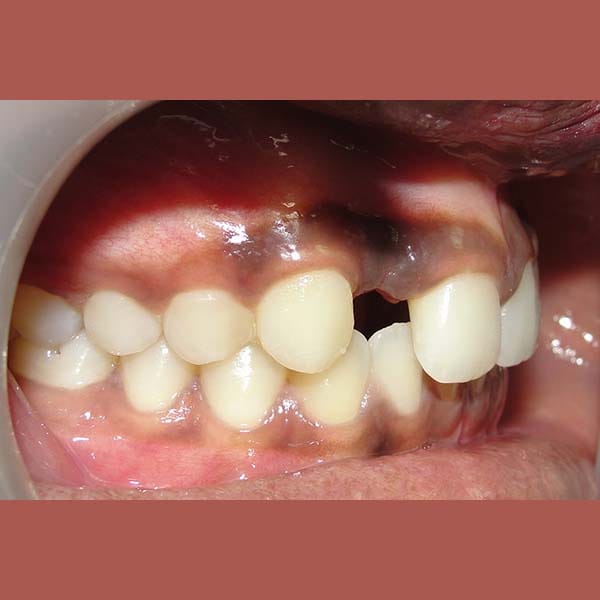

BEFORE